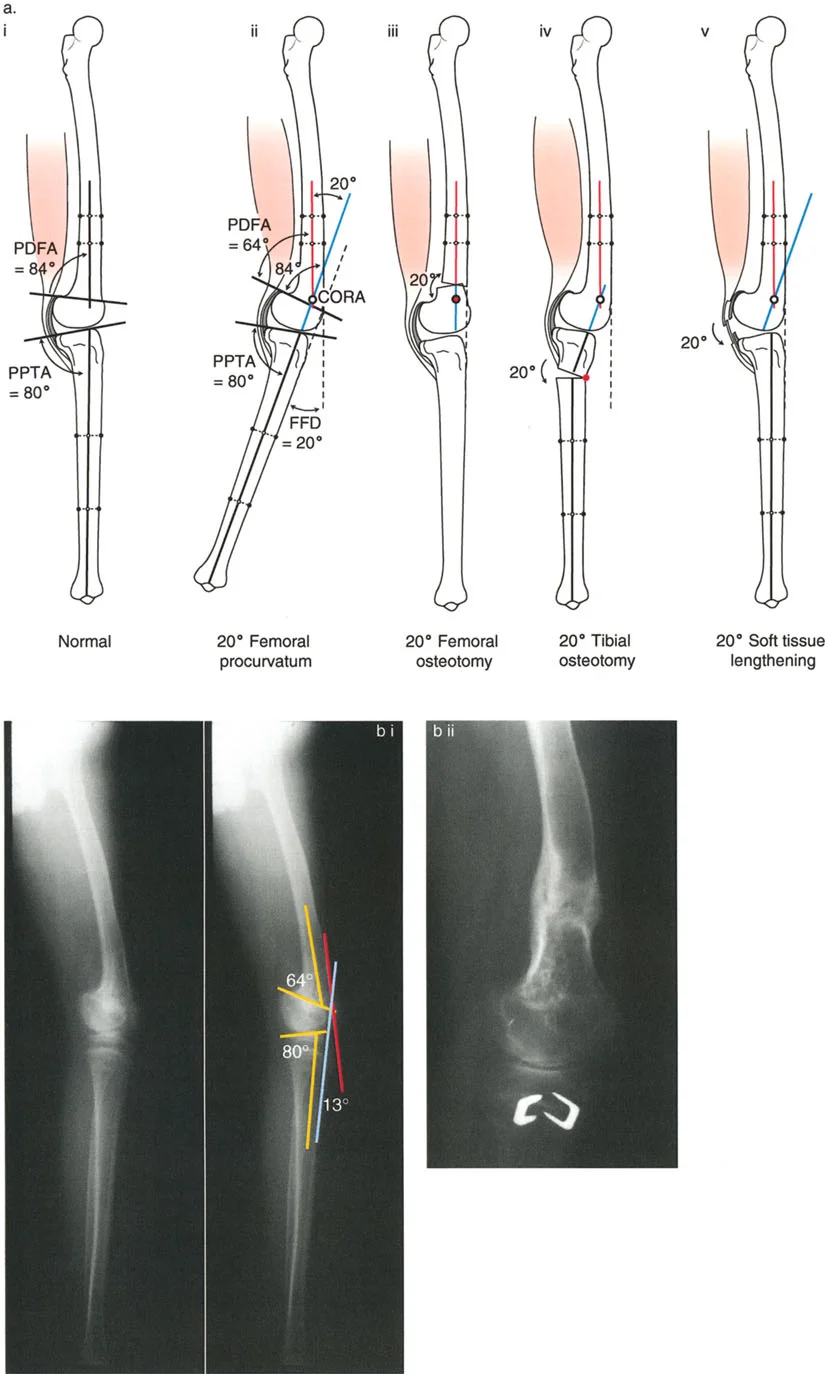

- تحدُّد حركة الركبة (Flexion Deformity - FFD): عدم القدرة على مد الركبة بالكامل، بحيث تظل الركبة في وضعية انثناء جزئي حتى عند محاولة فردها. يمكن أن يكون هذا ناتجًا عن تشوهات عظمية (مثل تقوس عظم الفخذ أو الساق للأمام) أو تقلصات في الأنسجة الرخوة (الأوتار والعضلات).

- الأشعة السينية الطويلة للطرف السفلي بالكامل أثناء الوقوف (Standing Long-Leg AP View): تُعد هذه الأشعة حاسمة لتقييم المحاذاة الميكانيكية للطرف السفلي بأكمله. تُظهر بدقة درجة الانحراف الأفحج (Varus) أو الأروح (Valgus) وتساعد في تحديد مركز دوران التشوه (CORA).

- الأشعة الجانبية الطويلة للطرف السفلي بالكامل أثناء الوقوف في أقصى بسط (Standing Long-Leg Lateral View in Maximum Extension): تُستخدم لتقييم تحدد حركة الركبة (FFD) والركبة الارتدادية (Recurvatum)، وتحديد ما إذا كان التشوه عظميًا أو ناتجًا عن تقلص في الأنسجة الرخوة.

تصحيح تحدد حركة الركبة (Flexion Deformity - FFD)

تحدُّد حركة الركبة هو عدم القدرة على مد الركبة بالكامل. يمكن أن يكون سببه عظميًا أو ناتجًا عن تقلص في الأنسجة الرخوة.

- التشخيص الدقيق: يجب تحديد ما إذا كان تحدد الحركة ناتجًا عن تشوه عظمي (تقوس أمامي في الفخذ أو الساق) أو تقلص في الأنسجة الرخوة (الأوتار الخلفية، محفظة المفصل).

- قطع العظم التمديدي (Extension Osteotomy):

- إذا كان التشوه عظميًا، يتم إجراء قطع عظم تمديدي في عظم الفخذ أو الساق لتصحيح التقوس.

- الأستاذ الدكتور محمد هطيف يؤكد على أهمية عدم تصحيح الساق بأكثر من 90 درجة PPTA لتجنب فقدان الميل الخلفي الطبيعي للساق.

- تحرير الأنسجة الرخوة (Soft Tissue Release):

- إذا كان السبب هو تقلص الأنسجة الرخوة، فقد يتم إجراء إطالة للأوتار أو تحرير لمحفظة المفصل.

تصحيح الركبة الارتدادية (Recurvatum Deformity - Hyperextension)

الركبة الارتدادية هي فرط البسط في الركبة. غالبًا ما تكون غير مصحوبة بأعراض في الأشخاص ذوي العضلات السليمة، ولكنها قد تسبب مشاكل في حالات ضعف العضلات أو التشوهات العظمية.

- التشخيص: يجب تحديد ما إذا كانت الارتدادية عظمية (تقوس خلفي في الفخذ أو الساق) أو ناتجة عن رخاوة في الأنسجة الرخوة أو ضعف عضلي.

- قطع العظم الانثنائي (Flexion Osteotomy):

- إذا كان التشوه عظميًا (تقوس خلفي)، يتم إجراء قطع عظم انثنائي في عظم الفخذ أو الساق لتصحيح الارتدادية.

- الأستاذ الدكتور محمد هطيف يشدد على أهمية عدم استخدام قطع عظم الفخذ الانثنائي لتصحيح ارتدادية الساق، والعكس صحيح، لتجنب الانزلاق الخلفي أو الأمامي للركبة.

- اعتبارات خاصة: في المرضى الذين يعانون من ضعف عضلي (مثل شلل الأطفال)، قد يحتاج التصحيح إلى فرط تصحيح بسيط (overcorrection) إلى وضعية انثناء لضمان ثبات الركبة ومنع فرط البسط غير المتحكم فيه.